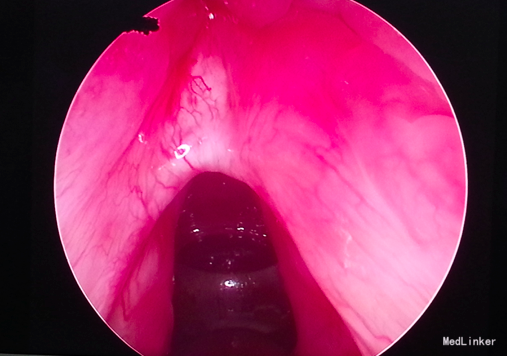

入院诊断:声带粘连 治疗:入院后全麻下行声带粘连部二氧化碳激光切除,局部安放喉膜,术后观察一周,术后三周去除喉膜。

本例为外伤后声带粘连,但日常预防声带粘连的关键是手术时尽可能 减少前联合创伤。手术时操 作一定要轻柔 , 避 免伤及前联合 。